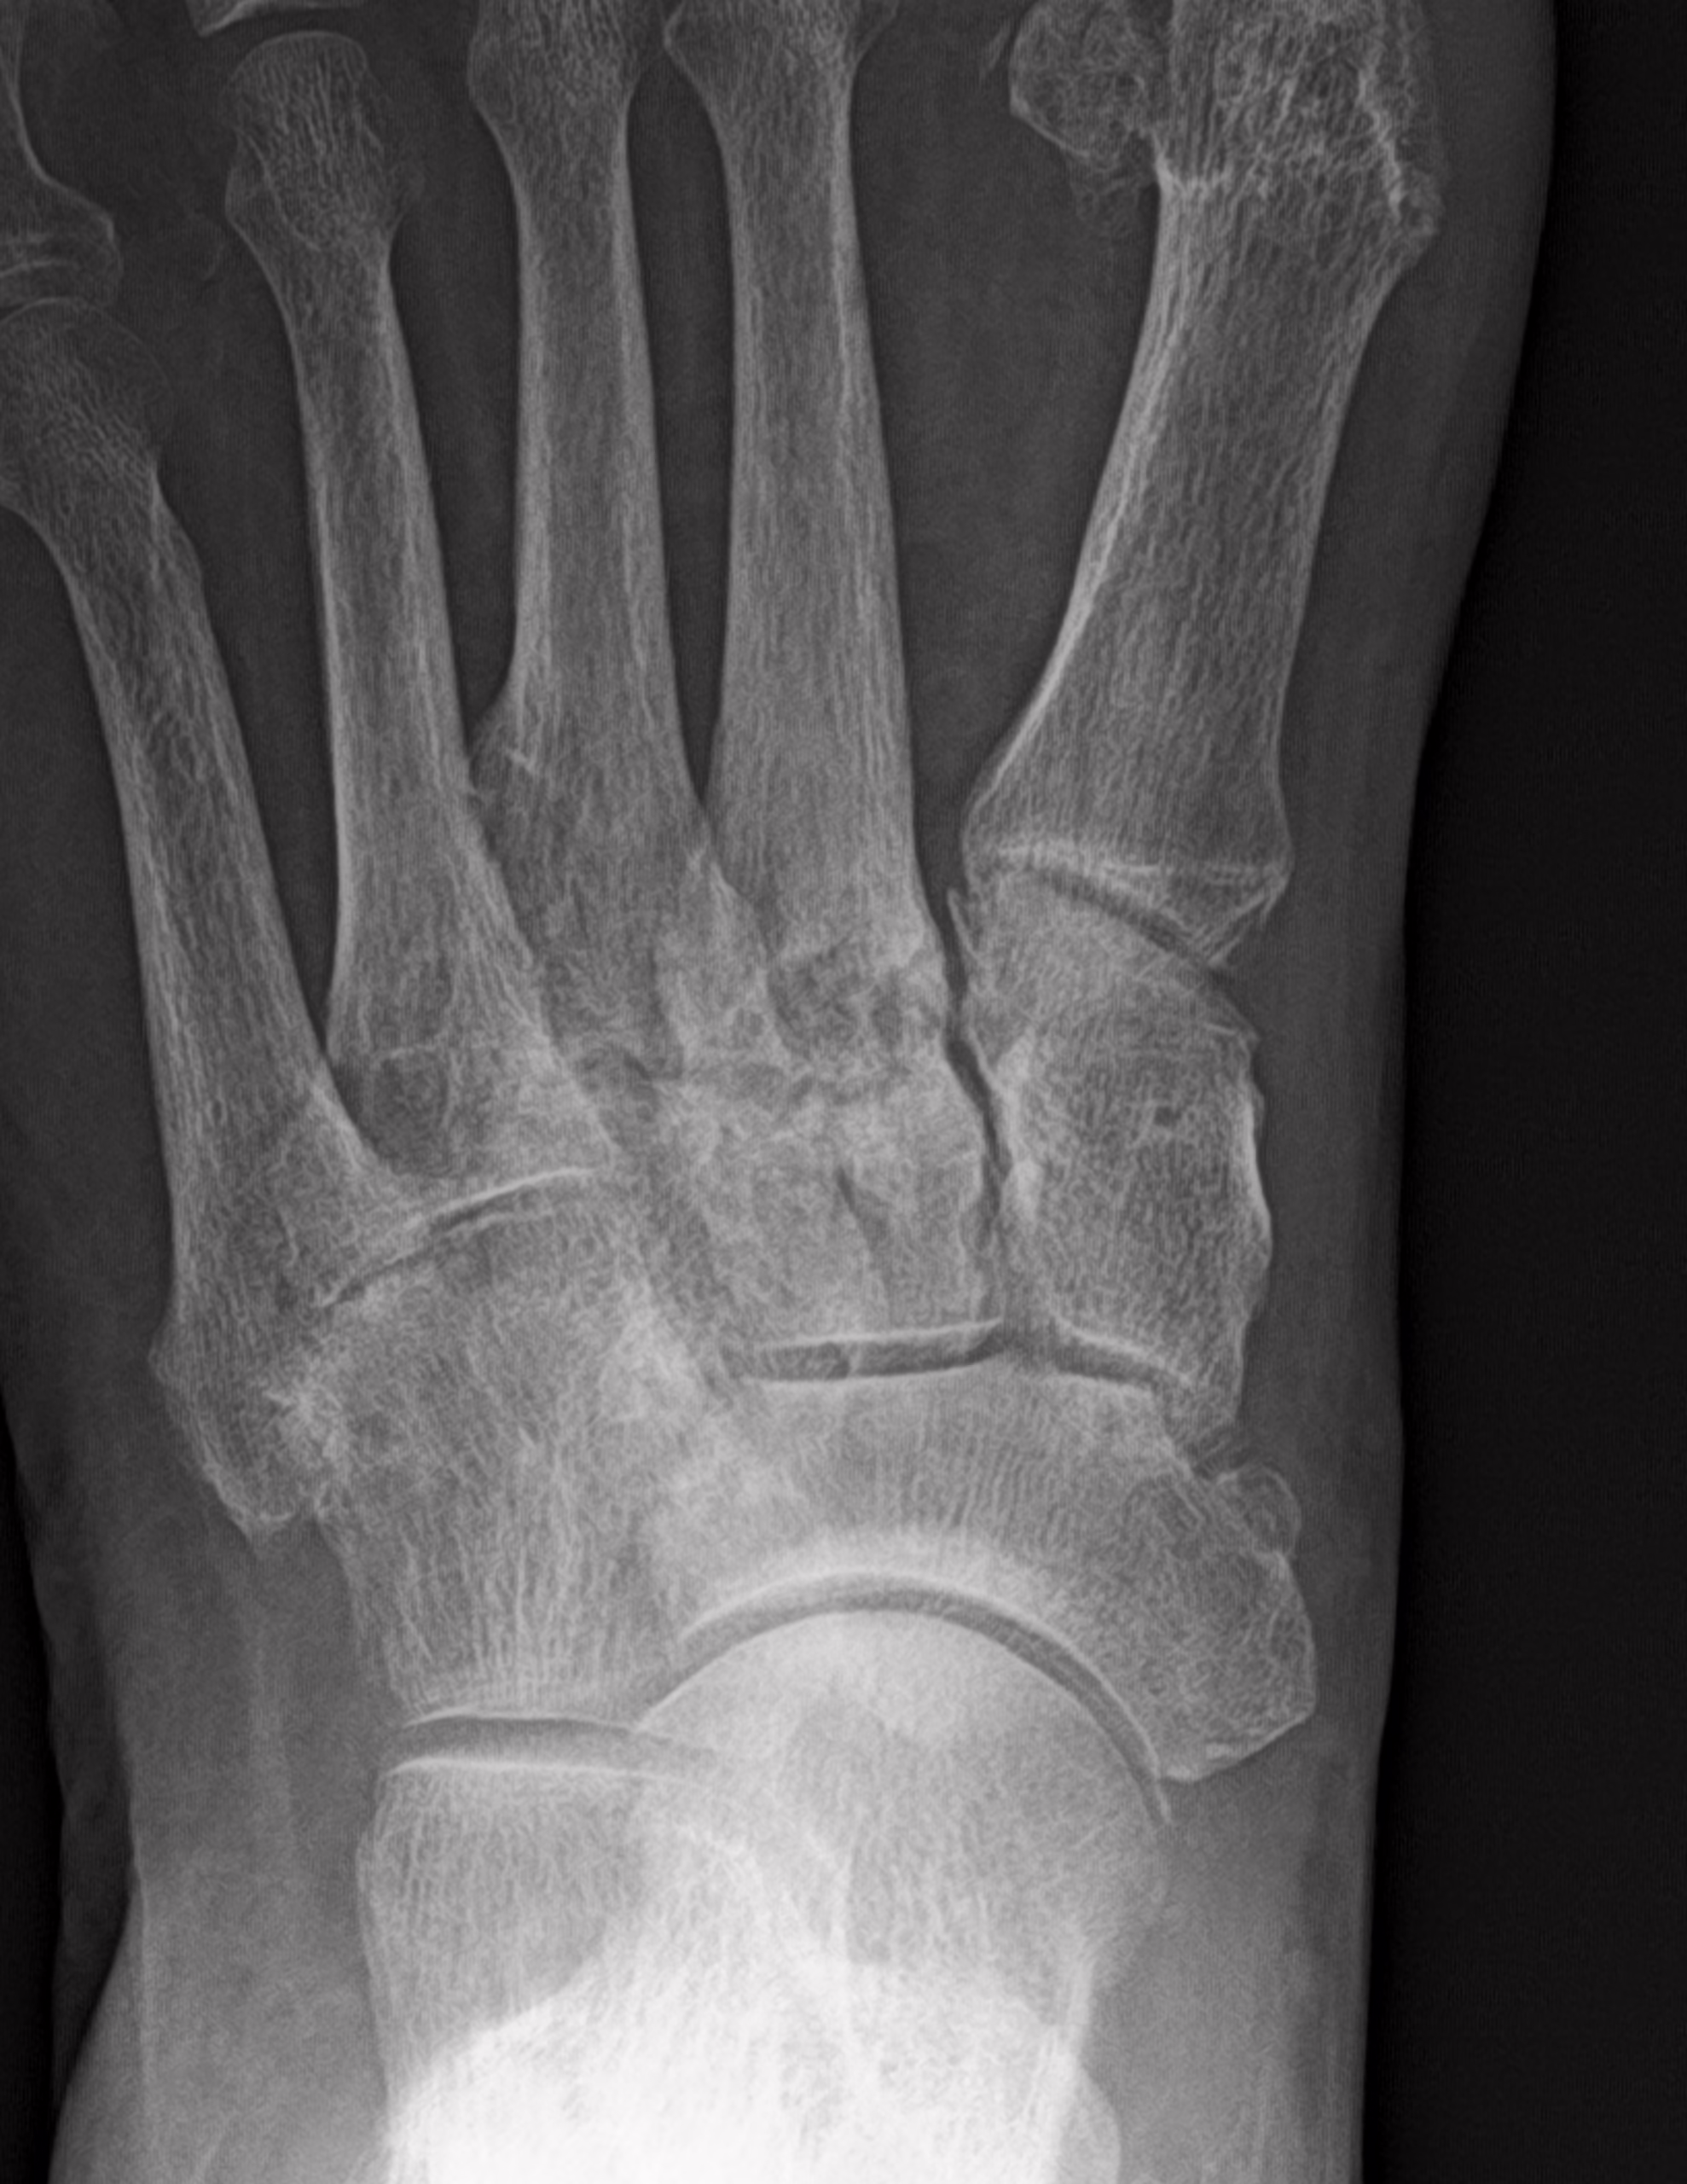

RADIOGRAFIA AP Y OBLICUA DE PIE

LAS PROYECCIONES RADIOLOGICAS OBTENIDAS NOS MUESTRAN LOS SIGUIENTES HALLAZGOS

-En lo observado de tibia y peroné, sin lesiones líticas, blásticas o perdida de la contigüidad.

-Se observa trayecto compuesto a nivel de proceso posterior del astrágalo. 2do cuneiforme con trazo longitudinal no desplazada. A nivel de base de 2do metatarso, con aparente fractura. Existe espícula osteofítica en porción inferior de tuberosidad del calcáneo. Resto de huesos del tarso, metatarsos y falanges, con disminución de la densidad, sin evidencia de lesiones líticas, blásticas o perdidas de la contigüidad.

-Espacios articulares, con adecuada amplitud

EN EL PRESENTE ESTUDIO RADIOGRÁFICO, EXISTE APARENTE FRACTURA DEL PROCESO POSTERIOR DEL ASTRÁGALO. FRACTURA DEL 2DO CUNEIFORME CON ASOCIACIÓN DE APARENTE FRACTURA NIVEL DE BASES DEL 2DO METATARSIANO, CON EDEMA ASOCIADO.

EXISTE ESPOLÓN ÓSEO DEL CALCÁNEO.

HALLUX VALGUS MODERADO.